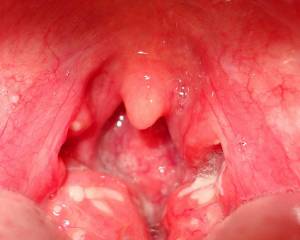

Если открыть рот и подышать им (тогда корень языка опустится), то по обе стороны от язычка, который свисает с неба, можно увидеть миндалины:

- большие (свободное расстояние между ними становится незначительным);

- красные;

- на поверхности видны налеты бело-желтого или сероватого цвета, которые расположены в естественных углублениях миндалин – лакунах.

Эти гнойники могут сливаться. При попытке их снять, легко удаляются, не вызывая повреждения подлежащих тканей или местного кровотечения.

Как выглядит горло при лакунарной ангине?

Ангина по форме течения: Горло красное, с небольшим отёком, фолликулярная — на поверхности миндалин появляются маленькие желтовато-белые гнойные пятна (гнойные фолликулы), лакунарная — гной скапливается в полостях миндалин (лакунах) и образует на их поверхности желтовато-белые пятна.

Какой налет при лакунарной ангине?

При лакунарной ангине гнойный налёт формируется в виде плёнок и отдельно локализованных мелких очагов и легко удаляется, после его удаления поверхность миндалины не кровоточит. При фолликулярной ангине миндалины сильно отекают и покрываются многочисленными желтовато-белыми бляшками гноя.